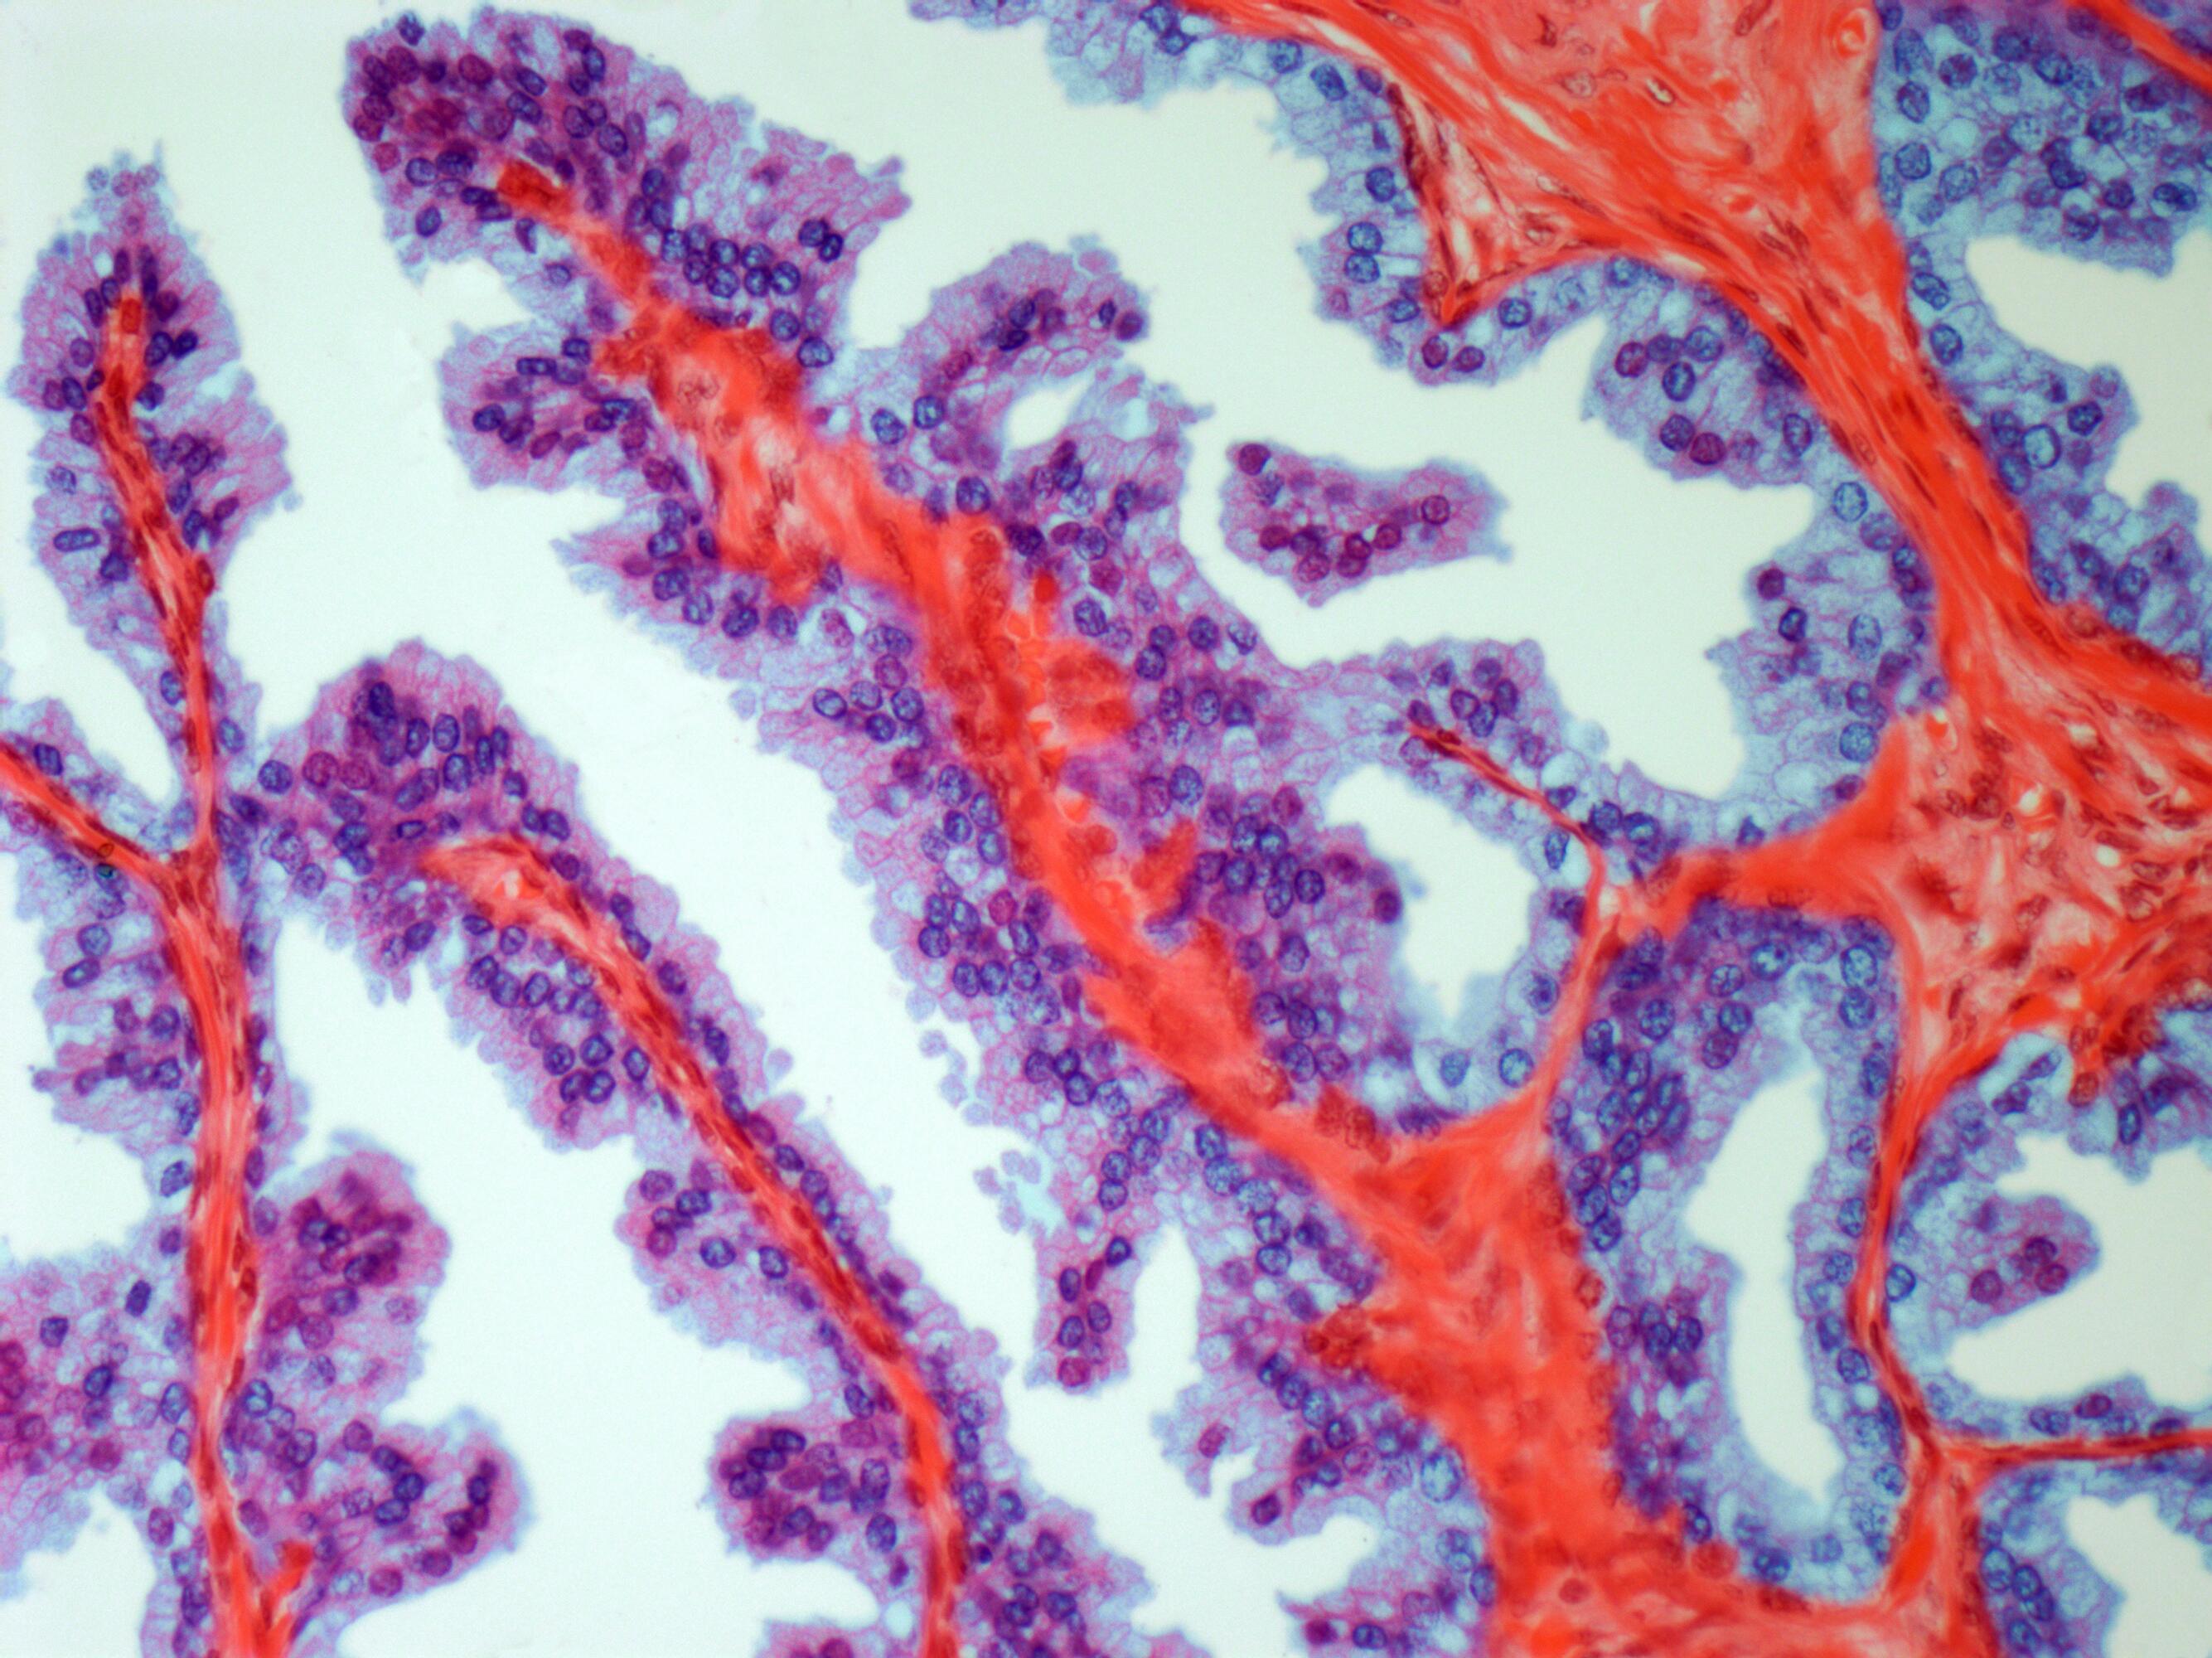

Bayer se dedică identificării și abordării nevoilor specifice ale persoanelor diagnosticate cu cancer de prostată, oferind terapii care le permit să navigheze prin fiecare etapă a bolii cu speranță și să își continue activitățile zilnice pentru o viață mai lungă și mai bună. Un pilon central al acestui portofoliu de inovație este darolutamida, un inhibitor oral al receptorilor androgenici (ARi) cu o structură chimică distinctă, care se leagă cu afinitate ridicată de receptorul androgenic și acționează ca un antagonist puternic, inhibând funcția și proliferarea celulelor cancerului de prostată. Studiile preclinice sugerează un potențial redus de traversare a barierei hemato-encefalice. De asemenea, produsul este aprobat în peste 70 de țări la nivel global.